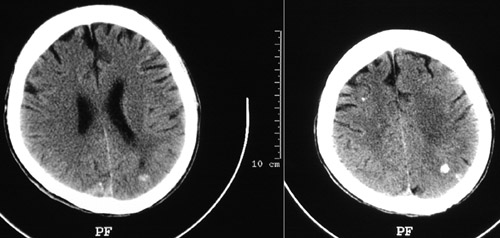

In this head CT scan views are bright foci that represent

septic emboli

in a patient with infectious endocarditis and a positive blood culture for

Staphylococcus aureus

.